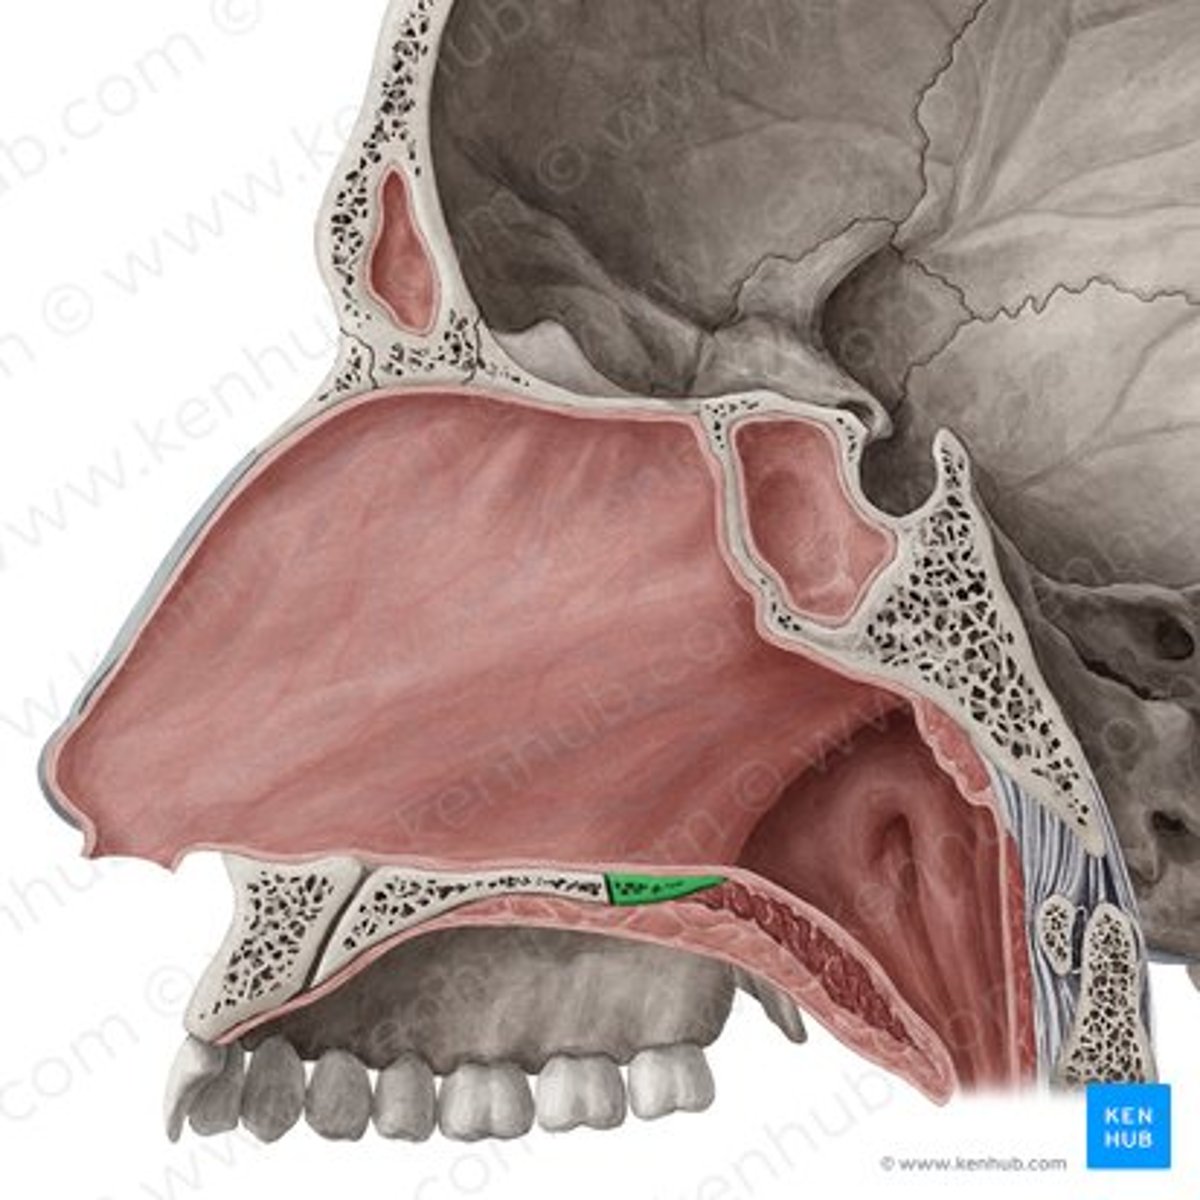

palatine bone (horizontal plate)

maxilla (palatine process)

nasopalatine nerve

descending palatine artery

greater palatine nerve

greater palatine artery

greater palatine foramen

lesser palatine nerve

lesser palatine artery